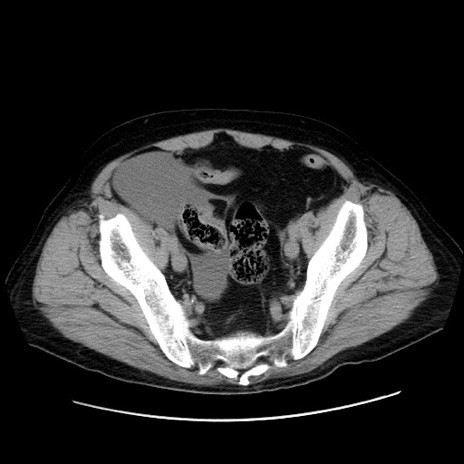

症例30(横断像)

【症例】80歳代男性

【主訴】臍周囲痛

【現病歴】約6時間前から臍下部痛が出現。次第に腹部膨隆・背部痛も生じてきたため来院。背部痛の場所は変化しない。

【身体所見】意識清明、BT 36.3℃、BP  131/87mmHg、P 87bpm、SpO2 100%(RA)、臍周囲自発痛・圧痛あり、反跳痛なし、自発痛部位に一致して板状硬あり、腹部膨隆、腸雑音減弱、CVA tenderness両側陰性。

【データ】WBC 19600、CRP 0.33